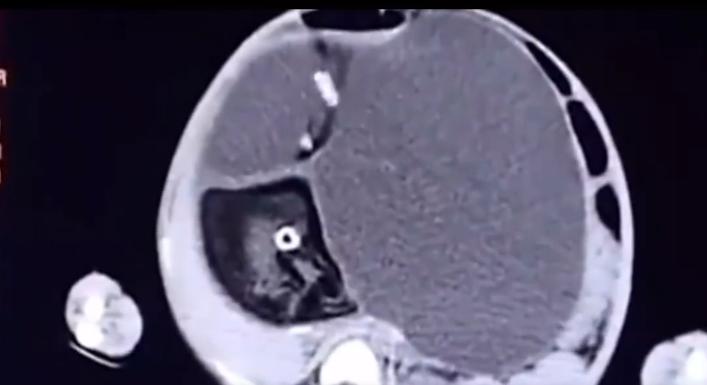

医生紧蹙着眉头,看着手里小梦茹的B超片子。

从片子上能够明显的看出,小梦茹腹中的胎儿已经成型了。

经过进一步的检查,和医生多方会诊,最终判定小梦茹肚子里这个是寄生胎。

由于小梦茹年纪太小,而且体内的寄生胎已经发生恶性变化,所以此次手术十分危险。

由于寄生胎在小梦茹体内牵扯太多组织,医生不得不小心翼翼的把它一点一点的剥离出来。

从小梦茹体内取出的寄生胎足足有五斤重,几乎占了小梦茹体重的一半。

据医生推测,这应该是小梦茹的亲生母亲在怀她的时候,其实是怀的是双胞胎。

而在母亲的子宫里,两个胎儿其实是竞争对手。

由于母亲输送的营养是一定的,两个胎儿就会互相争强母体的营养,以保证自己能够顺利存活下去。

相对强壮的胎儿为了争夺母体的营养,就会遏制另一个胎儿的发育,甚至将对方的胚胎吸收包裹进自己的体内。

于是,就形成了寄生胎,而寄生胎在寄主的体内仍是一个活的组织,只是等待时机,伺机而动。

所以,小梦茹体内的寄生胎,其实也就是当初她亲生母亲怀的另一个胎儿。